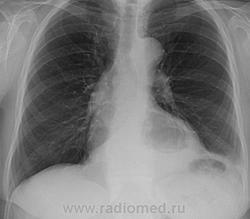

Флюорография органов грудной клетки: Лёгкие без очаговых и инфильтративных изменений. Умеренно выраженное усиление и деформация легочного рисунка, за счёт явлений пневмосклероза. Сердце несколько расширено в поперечнике. На фоне тени средостения определяется дополнительное полостное образование, вероятно кардиофундальный отдел желудка.

Рентгенологически: больше данных за фиксированную грыжу пищеводного отверстия диафрагмы, для уточнения рекомендована рентгеноскопия желудка.